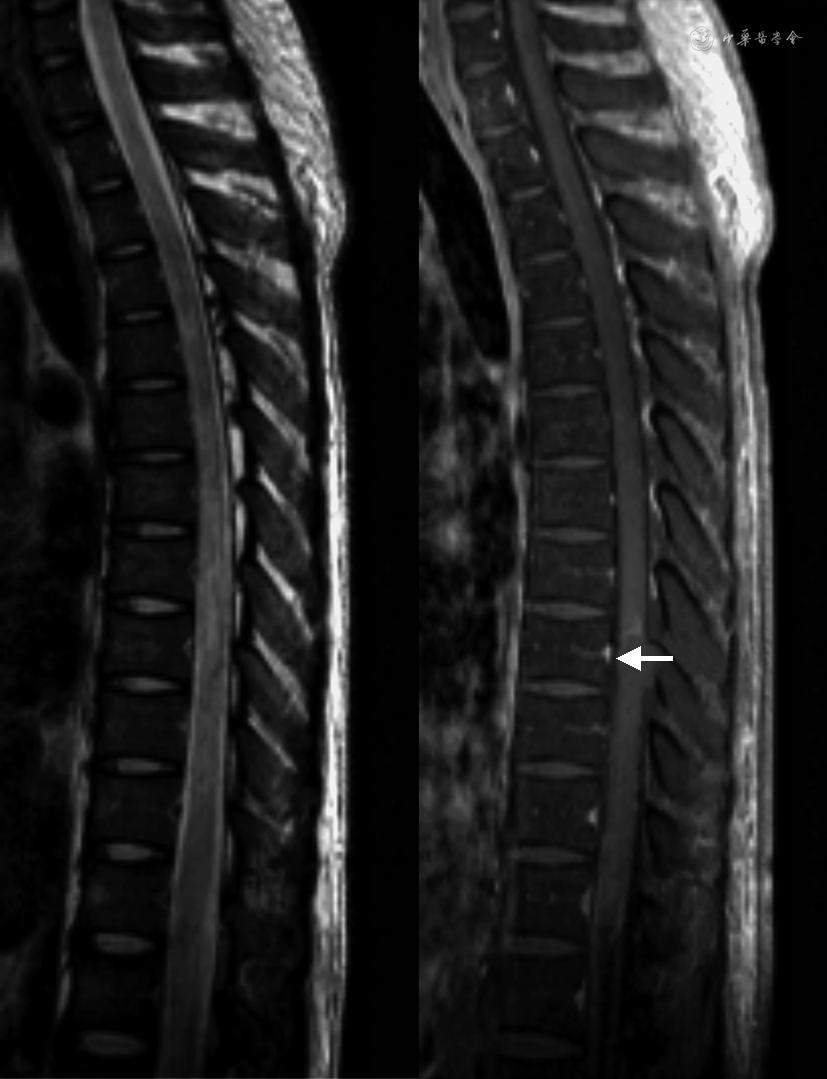

本患者口服虫螨-茚虫威20 ml后,出现发热、出汗及截瘫等症状,期间未出现呼吸困难、口唇黏膜、甲床紫绀等症状,据临床表现推测其可能为虫螨腈中毒,原因如下:首先,虫螨-茚虫威混合制剂中茚虫威浓度远远低于虫螨腈;其次,茚虫威的毒性明显小于虫螨腈且茚虫威具有低哺乳动物毒性的特点[18]。本患者中毒后血磷酸肌酸酶、乳酸脱氢酶、肝酶基本恢复正常,仅遗留截瘫,表明重要脏器(如肝脏、肌肉)等基本不受影响,以神经系统损害为主;结合肌电图提示周围神经未见明显异常,因而损害主要为CNS。根据影像学证据,经复习文献,目前仅见4例人类虫螨腈中毒并累及CNS报道,MRI均表现为长T1长T2,液体衰减反转恢复(FLAIR)序列、DWI高信号,表观弥散系数(ADC)低信号的双侧大脑半球白质束对称性病变及全脊髓弥漫性肿胀[7, 8,19,14]。本患者头颅MRI(图1)在T2WI上突出表现为广泛性和对称性的高信号改变伴明显弥散受限,其异常信号局限于整个大脑、脑干的白质及脊髓MRI(图2),提示胸髓可疑肿胀,与既往报道的虫螨腈中毒并累及CNS的影像结果非常相似。综上所述,本患者虫螨-茚虫威中毒后的临床症状、影像学特点均与既往病例报道的人类虫螨腈中毒的临床影像表现相符,因此最终考虑其为虫螨腈中毒。

人类虫螨腈中毒易导致CNS白质病变的机制目前尚不清楚,推测原因如下:首先,虫螨腈属于较强的脂溶性亲神经毒物,容易透过血脑屏障;其次,虫螨腈影响细胞能量代谢,且CNS本身代谢旺盛,能量消耗大,因此CNS比人体其他组织更易受虫螨腈的干扰;再次,与CNS的灰质相比,白质更容易受亲脂类毒素的破坏[20],因此最终虫螨腈中毒累及神经系统以广泛CNS白质病变为主。CNS白质病变常见的病理改变为脱髓鞘[21],本患者脑脊液及血清脱髓鞘抗体水通道蛋白4-IgG、髓鞘少突胶质细胞糖蛋白-IgG、神经胶质纤维酸性蛋白-IgG、IgG-寡克隆区带均为阴性,暂时能排除其CNS白质病变为原发性免疫介导的CNS炎性脱髓鞘。近来de Oliveira等[22]总结了常见中毒代谢性脑病的影像学特点,发现不累及灰质的弥散受限、非强化的弥漫性对称性脑白质病灶多数是可逆的,其病理改变可能为髓鞘内水肿。Baek等[14]报道了1例口服极少量10%的虫螨腈19 d后出现截瘫,MRI呈FLAIR、DWI高信号,ADC低信号且非强化的双侧对称性弥漫脑白质病变以及全脊髓肿胀的幸存患者,中毒71 d后其MRI表现为脑及T7以上脊髓异常信号完全消失,T7以下脊髓残留高信号及萎缩改变;该患者CNS白质异常信号消失的特点表明虫螨腈中毒性CNS白质病变可逆。同时也有研究者对虫螨腈中毒后的大鼠神经组织行病理活检,发现其神经髓鞘轻度肿胀[14]。由此可见,虫螨腈中毒性CNS白质病变极有可能为可逆性髓鞘内水肿。本例患者虫螨腈摄入剂量、截瘫的临床症状以及MRI特点均与Baek等[14]报道的虫螨腈中毒患者十分相似,因此推测其虫螨腈中毒性CNS白质病变为可逆性髓鞘内水肿。遗憾的是,由于经济条件受限,本患者出院后拒绝复查MRI,其中毒后第8天和第19天的MRI检查结果提示异常信号未消失,可能由于复查MRI的间隔时间过短。随访至今本患者仍遗留截瘫症状,推测可能与MRI提示T9椎体平对脊髓片状强化、不可逆损害有关。本例患者与Baek等[14]报道的患者虫螨腈中毒后分别出现T9、T7脊髓的不可逆病灶,表明胸髓比其他脊髓节段更易受毒物影响,推测可能与胸髓血供较其他脊髓节段稍差有关。